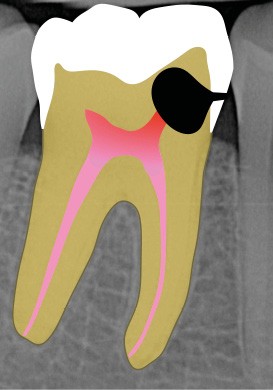

Perforation infra-osseuse avec accès visuel direct (fig. 3)

Ce type de perforation est également la plupart du temps iatrogénique et survient lors de la recherche ou de la mise en forme canalaire, lors de la préparation pour un logement de tenon radiculaire. Situées au niveau du plancher pulpaire des dents pluriradiculées, ou au niveau des entrées canalaires des dents monoradiculées ou pluriradiculées, il s’agit le plus souvent de perforations à quatre parois. Si la perforation survient en cours de traitement, elle doit être gérée immédiatement pour un meilleur pronostic (fig. 4). Néanmoins, il est important de prendre en compte l’épaisseur résiduelle du plancher. Si le plancher est trop fin, il ne sera pas possible d’envisager de traiter la perforation.